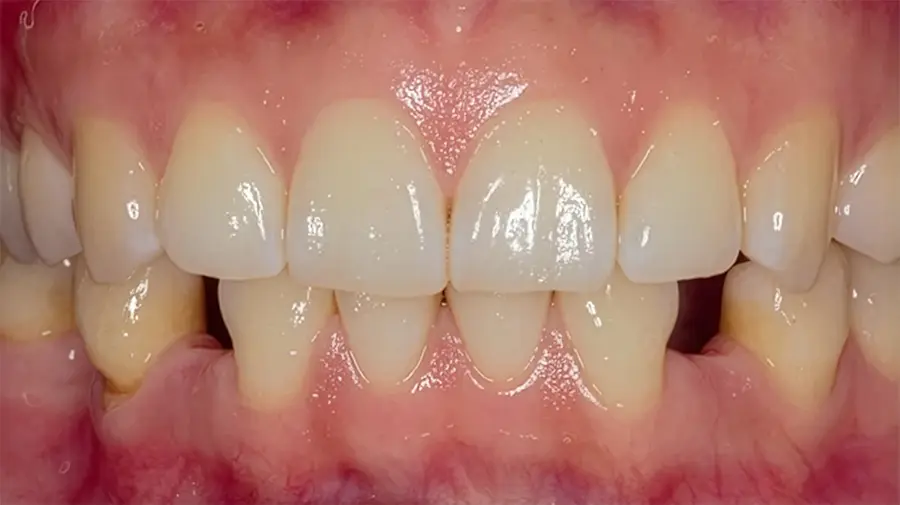

Una vez integrado, se coloca la pieza dental definitiva, diseñada para reproducir forma, color y función de los dientes naturales.

La diferencia de recuperar tu sonrisa

«No estamos sustituyendo dientes, estamos devolviendo la capacidad de disfrutar de un buen momento alrededor de una mesa sin preocupaciones.» — Dr. Esteban Balabanian